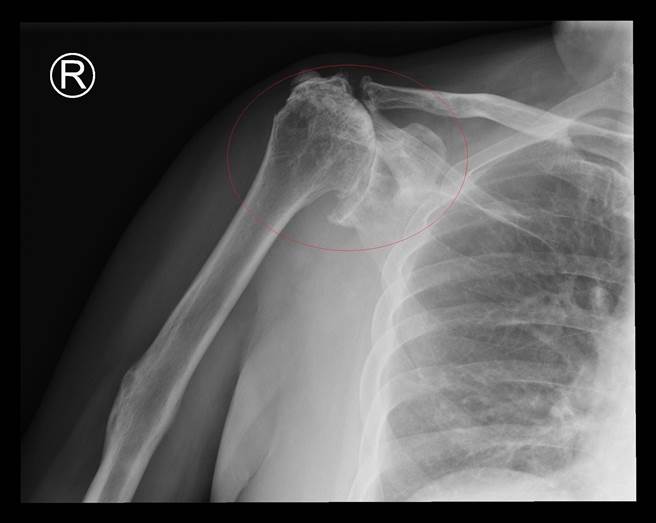

陈柏辰指出,旋转肌最主要的功能就是让肩膀能抬高伸展,还有内外旋转,当旋转肌破裂后无法自行癒合,就会产生疼痛、手不举的症状,许先生因为长年未对症下药,还造成关节退化、骨头移位,使得肱骨头和肩峰摩擦加剧疼痛。

陈柏辰说,两者的症状确实很像,但五十肩是关节沾黏,与旋转肌破裂不同,许先生经过反制是肩关节置换后,4天就出院,现在已经可以拿东西,自行穿脱衣服,恢復原本健康正常的生活,提醒民眾发生类似情形还是要找专业医师就诊,找出原因才能对症下药。